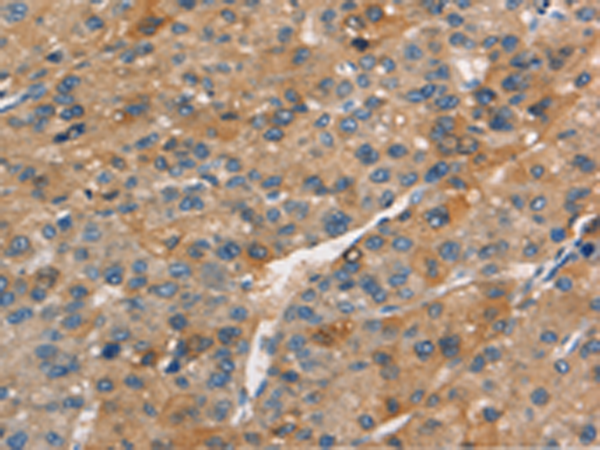

分类: 科研抗体货号: P11193别名: AIBP; PEBEL; YJEFN1; APOA1BP应用: IHC反应种属: Human, Mouse, Rat